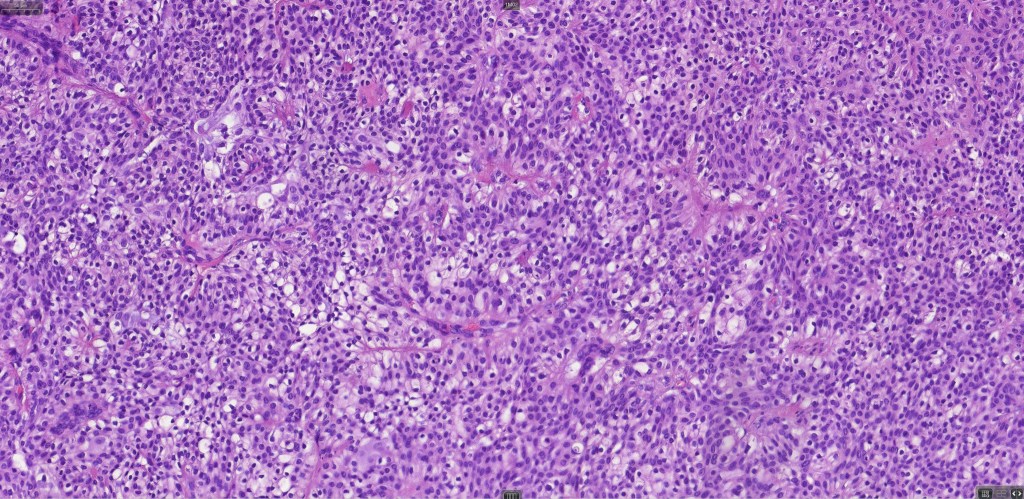

•Hidroacanthoma represents a wholly intraepidermal population of small poroid cells sharply delineated from the adjacent larger keratinocytes

•Careful scrutiny and often levels are required to reveal intracytoplasmic lumina or ductal differentiation

•In poroma, a dermal-centric tumor is associated with epidermal origin/continuity & is composed of small cells with vesical nuclei.

•Desmosomes often prominent

•Clear cells (sometimes predominating- so-called clear cell variant)

•No peripheral palisading or retraction artifact

•Variable squamous differentiation (can be marked)